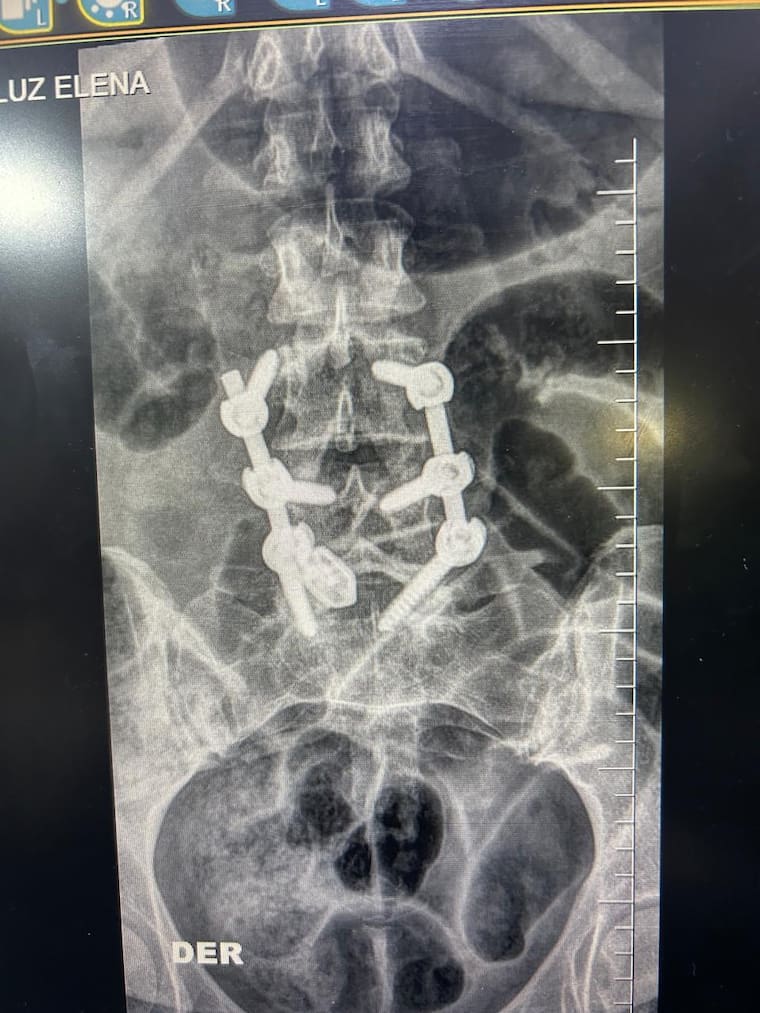

La paciente fue, Luz Elena Morelos Gandía, procedente del municipio de Fonseca, sur de La Guajira, quien tenía una enfermedad degenerativa de uno de sus discos en la columna vertebral por lo que debió ser sometida a la cirugía de artrodesis lumbar con instrumentación para estabilizar la columna vertebral y aliviar el dolor.

“Durante la cirugía no hubo complicaciones, se presentó poco sangrado, obtuvimos muy buenos resultados y la paciente ha tenido una evolución satisfactoria”, dijo el ortopedista.